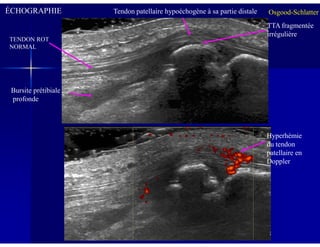

Échographie:

Si TTA cartilagineuse: tuméfaction hypoéchogène,

Osgood-Schlatter

Si TTA ossifiée: aspect fragmenté et irrégulier

Épaississement hypoéchogène de la partie distale du tendon

patellaire

Bursite prétibiale profonde

ÉCHOGRAPHIE

TENDON ROT

NORMAL

Tendon patellaire hypoéchogène à sa partie distale

Bursite prétibiale

profonde

TTA fragmentée

irrégulière

Hyperhémie

du tendon

patellaire en

Doppler